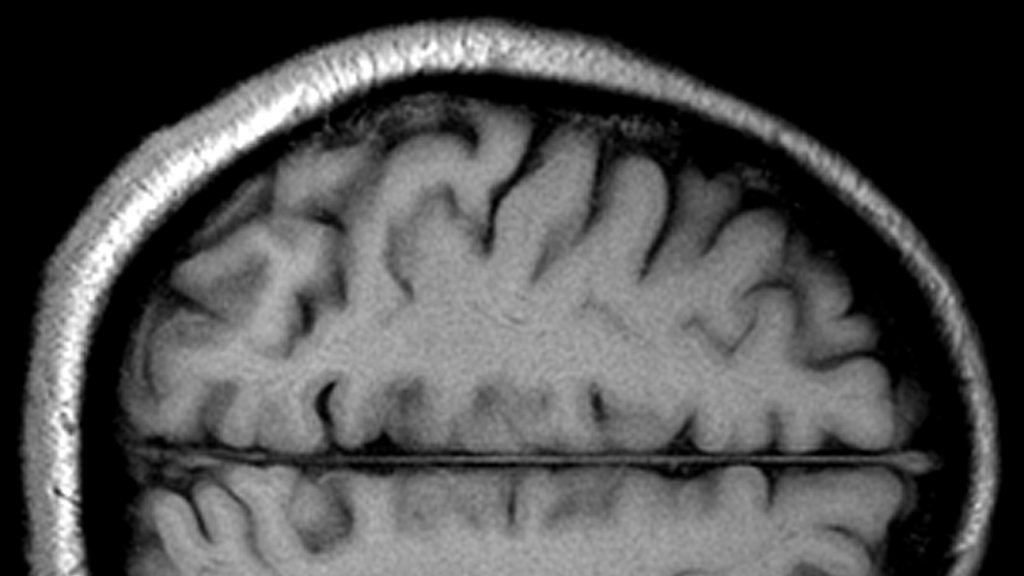

A young Colin Blakemore's Reith Lecture: Understanding the human brain is more important than understanding the frontiers of space or the inside of an atom.